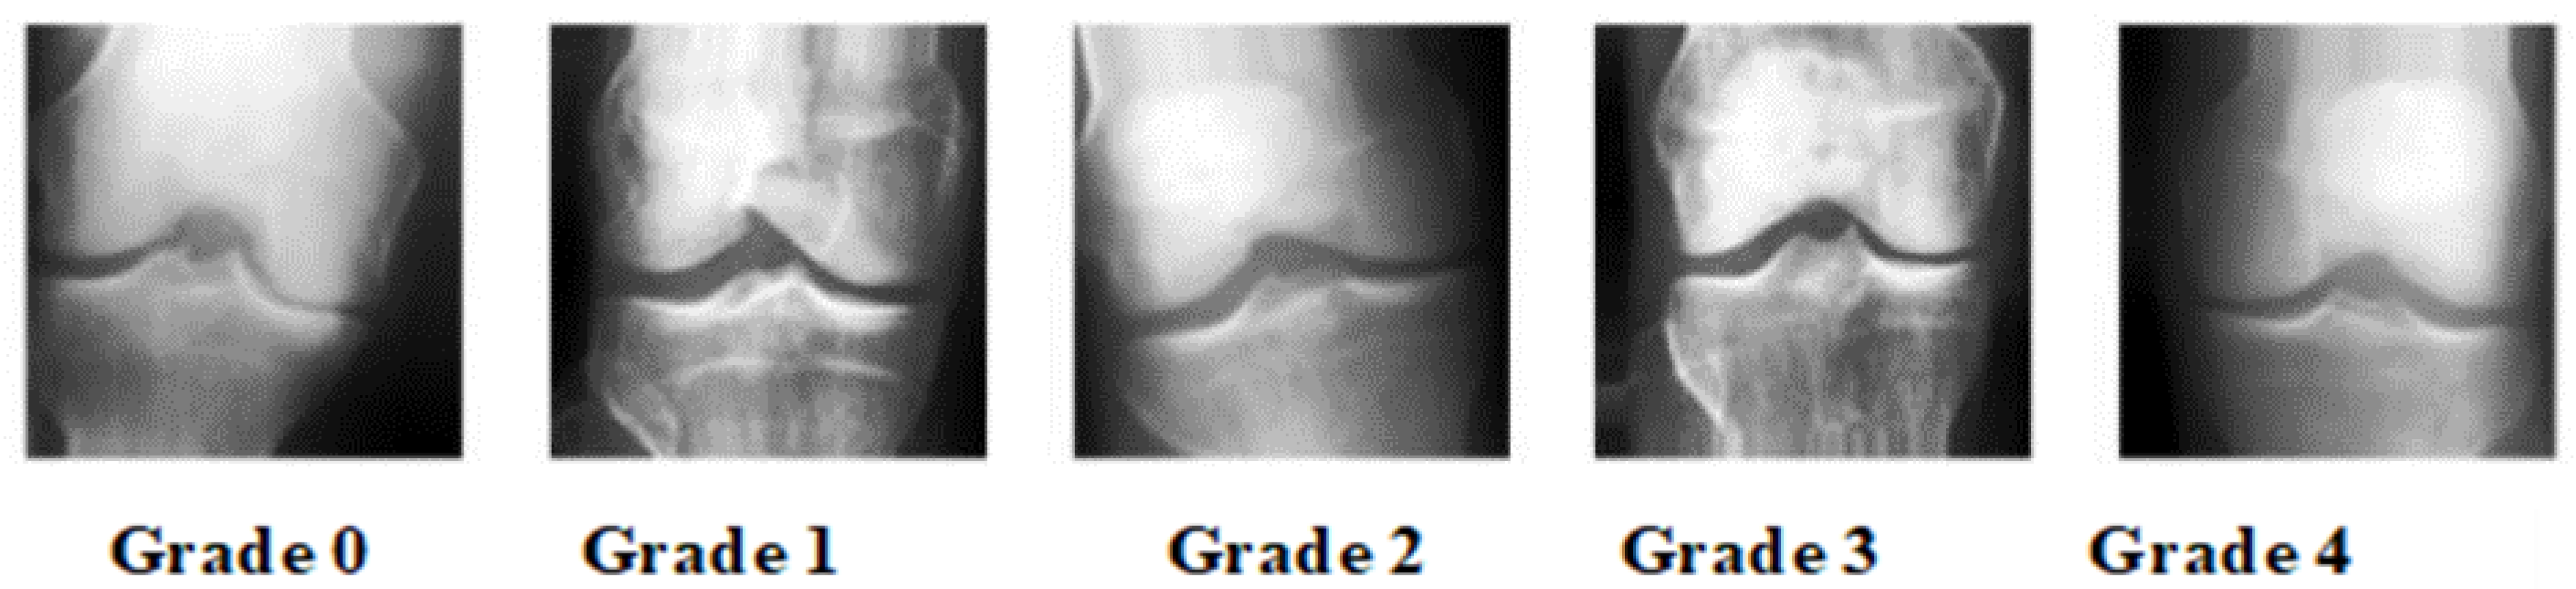

- Grade 0: knee appears to be in good health in this photograph.

- Grade 1 (Unlikely): Possible osteophytic lipping with joint narrowing.

- Grade 2 (Minimal): Definite presence of osteophytes and possible joint space narrowing.

- Grade 3 (Moderate): Osteophytes, joint space narrowing, and mild sclerosis are all signs of disease.

- Grade 4 (severe): Osteophytes, joint constriction, and extensive sclerosis are all present in patients with disease.